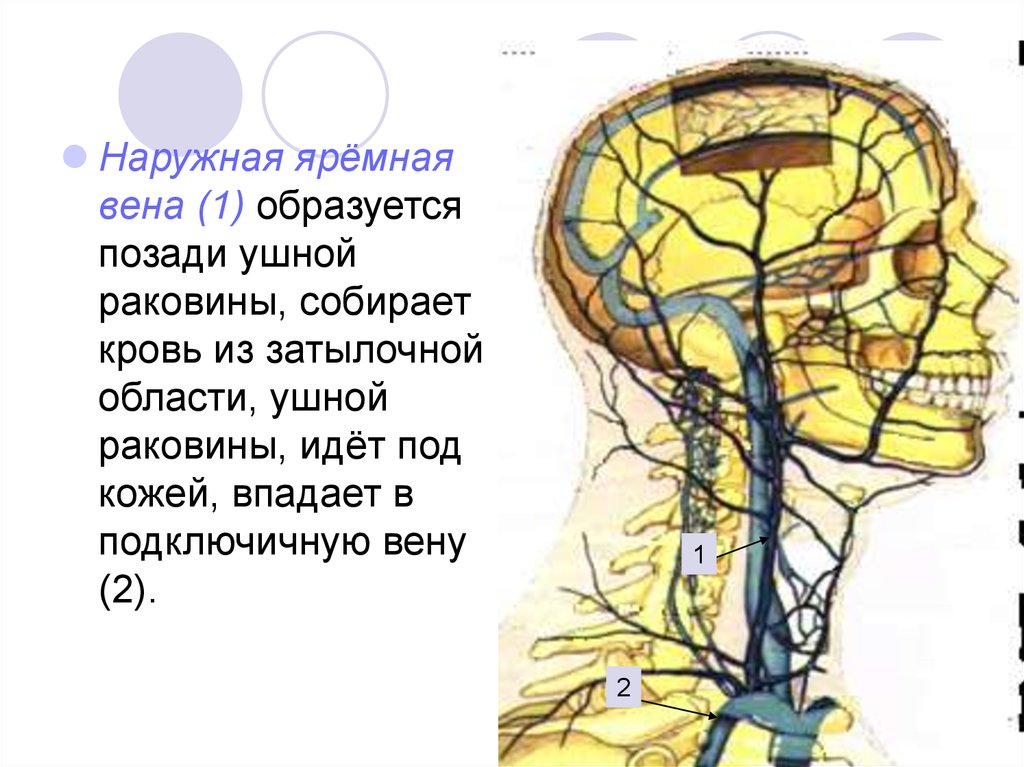

Анатомия внутренней яремной вены: КТ изображения